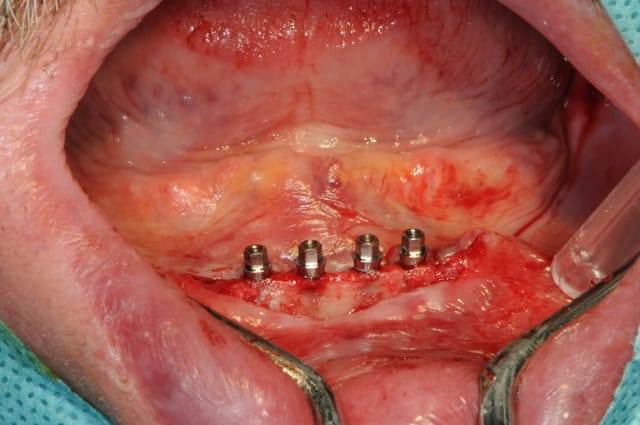

Bon, je viens de lui poser ses 4 mini-implants ce matin.(diamètre2.8 longueur 13mm)

je crois que comme ils ne sont pas trop mal disposées, je vais les solidariser par une barre d'Ackerman plutôt que 4 boules.

plus distalement, il y avait un os en néoformation donc insatisfaisant pour une stabilité primaire des implants, mais surtout, le relief osseux était désastreux.

en fait la plastie à été faite sur 3 bon millimètres et je ne trouvais pas la position distale vraiment alléchante.

parfois c'est une sensibilité propre en cours d'intervention qui modifie un peu le plan de traitement.